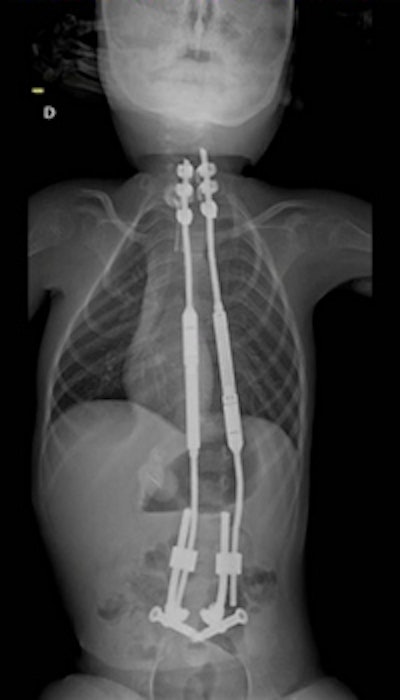

X-ray displaying spinal stem implants.The team used their 3D-printed model of the child's spine to simulate a robot-guided minimally invasive procedure, which enabled them to perfect their timing and fine-tune their surgical precision. The challenge of inserting 7-mm iliosacral screws into a bone corridor that was 8-mm wide proved possible with the support of a robotic surgical assistant (ROSA, MedTech).